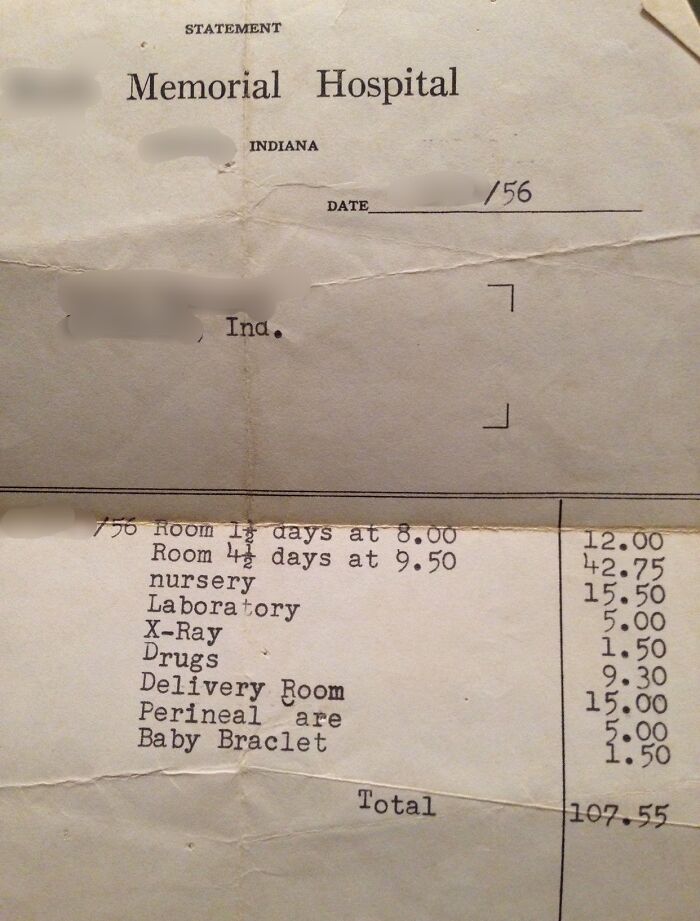

#69 The 1956 Hospital Bill From When My Mom Was Born. 6 Day Hospital Stay. $107.55 Total

Image credits: stefanielaine